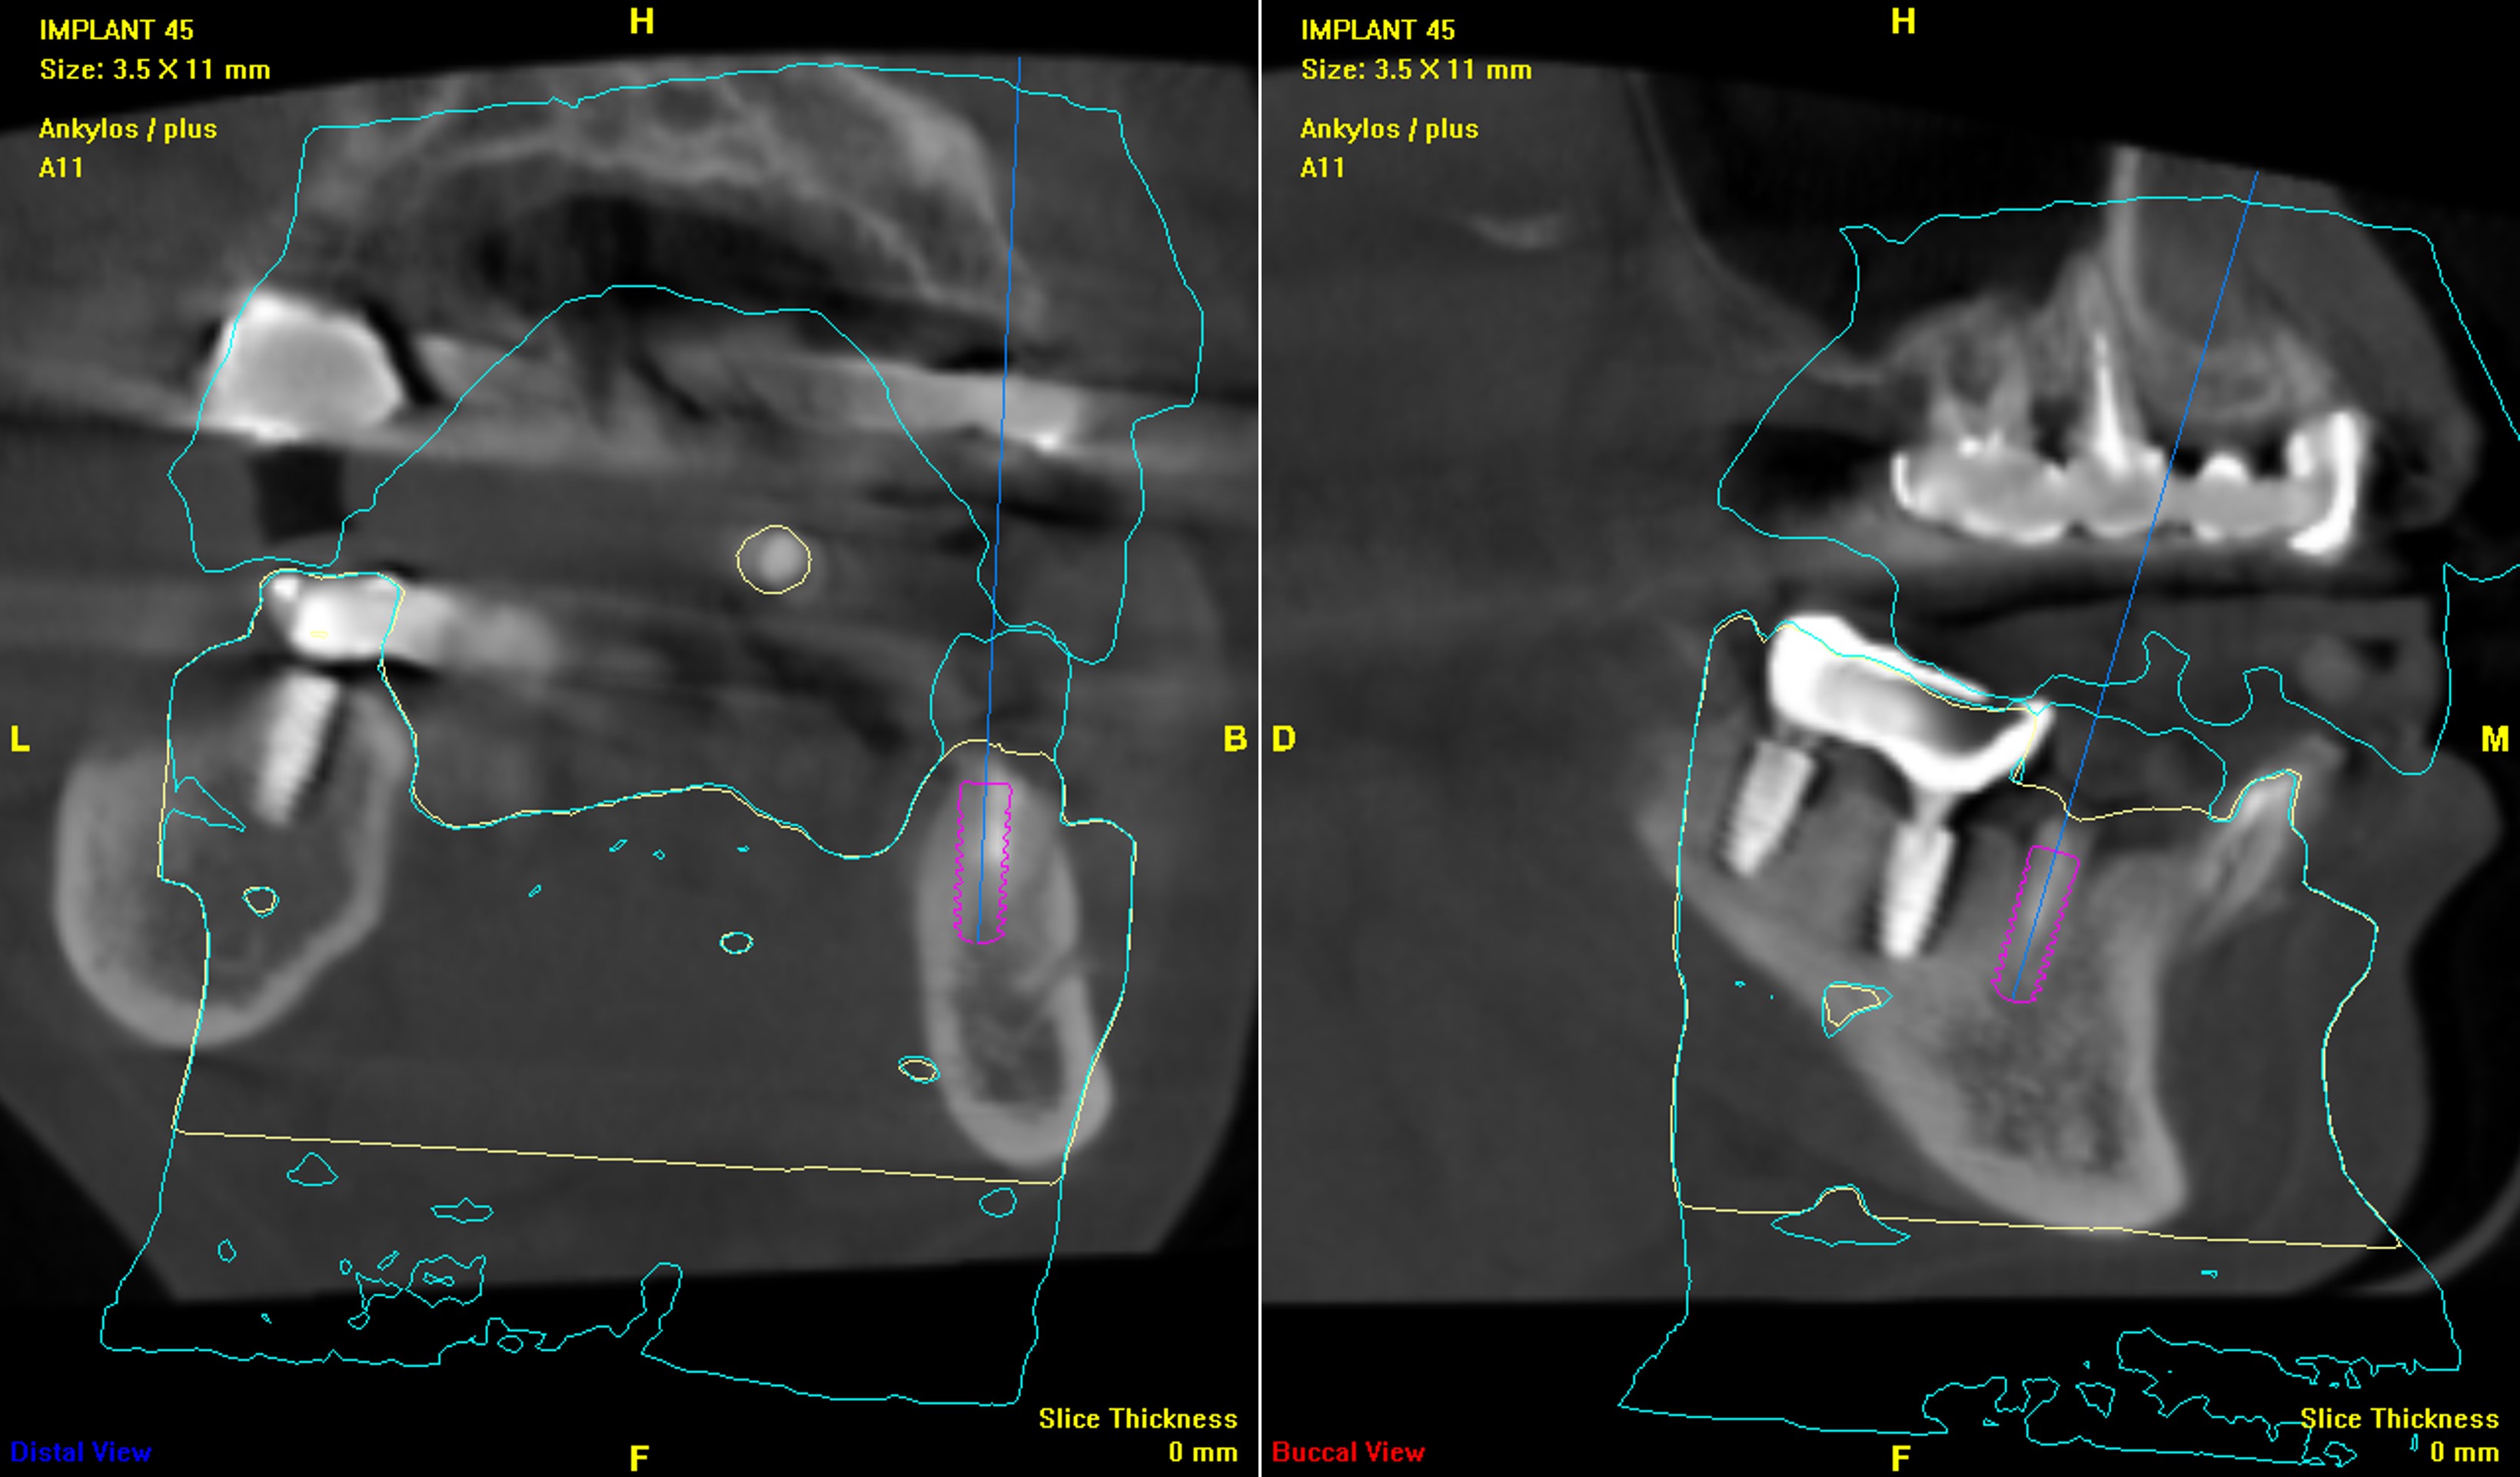

電腦斷層評估植牙位:#45